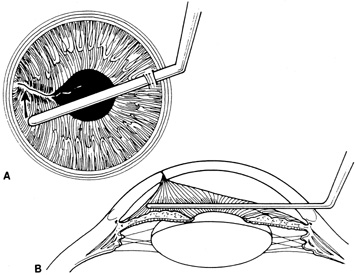

Incarcerated tissue will usually require mechanical reposition. Selected cases of mild incarceration may be treated with pharmacologic agents. Agents such as intraocular acetylcholine or carbachol cause pupil constriction, thus pulling iris from the wound. If incarcerated iris is located in the central cornea, mydriatic agents (e.g., intraocular epinephrine 1:10,000) may be used. If mechanical reposition is required, simply deepening the anterior chamber may release incarcerated tissue. Viscoelastic agents may be irrigated through the paracentesis port or the wound adjacent to the involved iris tissue in an attempt to draw the incarcerated iris from the wound (Fig. 12). If unsuccessful, a cyclodialysis spatula or irrigating canula may be passed through the paracentesis site and used to directly sweep incarcerated tissue free (Fig. 13). Care is always taken to avoid trauma to the corneal endothelium, iris, and lens. Any excised tissue should be sent to the pathology department for examination.